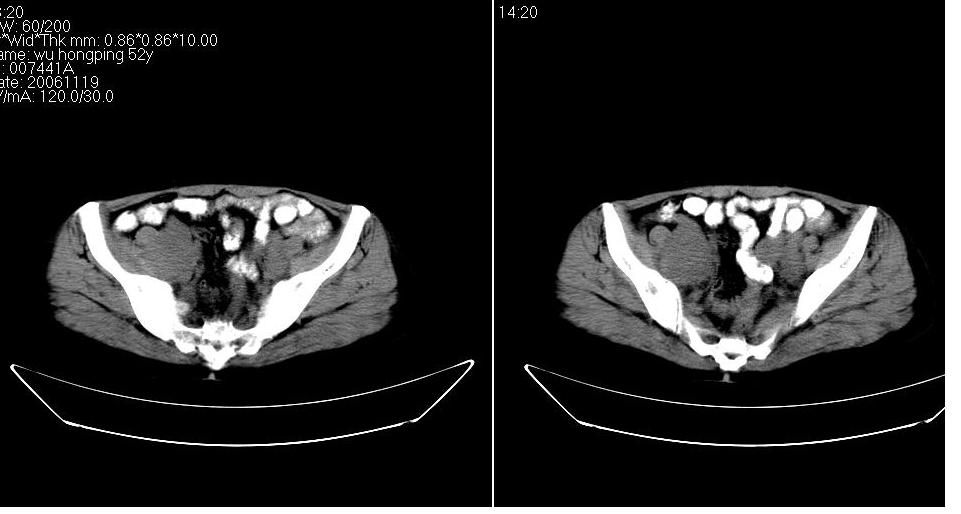

女 53岁,大便每天四到五次,变细,伴有粘液,病人家属说,去年五月在外院行子宫肌瘤术。

腹膜后多发肿大淋巴结肿大并融合改变;右侧回盲部可见团块样软组织影,不规则;

淋巴瘤?回盲部占位,,淋巴瘤肠道改变?建议进一步检查.

腹膜后诸多淋巴结,右侧髂窝软组织块影,综合患者大便次数、形状改变,考虑结肠回盲部肿瘤

盆腔内的肿块与升结肠没有什么关系,我考虑1来于小肠 2就是个融合的盆腔淋巴结 不能解释的是病人为什么大便变细,黏液便,会不会是直肠有浸润,我看直肠壁好象有点厚

回盲部可见团块样软组织影,不规则;腹膜后多发肿大淋巴结肿大并融合改变;考虑回盲部肿瘤并腹膜后淋巴结转移,建议钡剂灌肠或增强检查.

双侧盆腔均可见不规则形软组织肿块影,似为结节状影融合而成,但以右侧为甚,腹主动脉与下腔静脉周围亦可见多个肿大淋巴结.

结合临床手术史考虑:盆腔与腹膜后多发性淋巴结转移(原发灶可能是原来的\"子宫肌瘤\"恶变或并非\"子宫肌瘤\";回盲部肿瘤不排除)